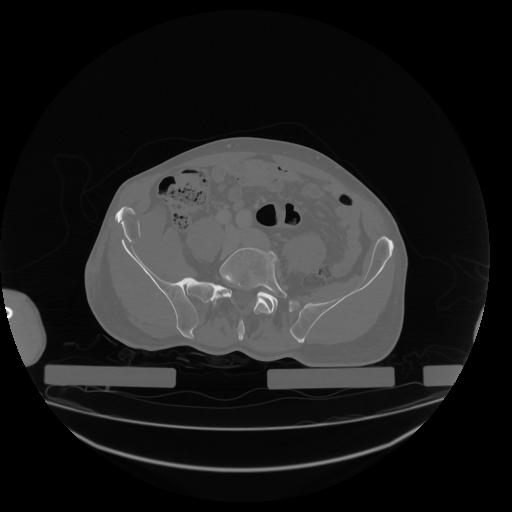

34 CUERPO,CE,Vol,1.0,CUERPO,,